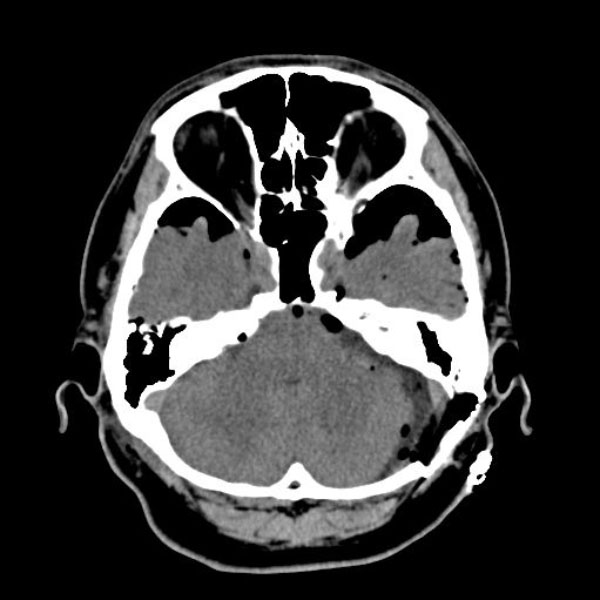

手術前

(MR1)

手術後

(CT)